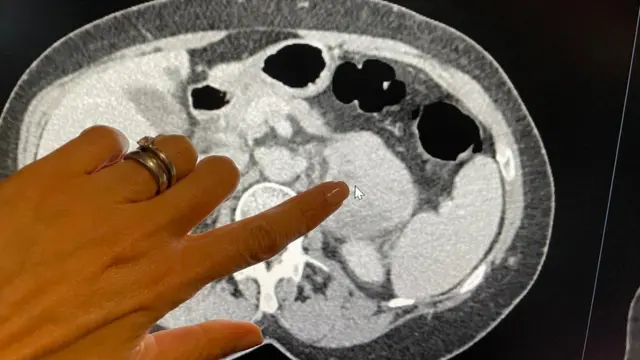

ओटीपोटाच्या मागील बाजूला जोडणा-या तंतूंमध्ये रेट्रोपेरिटोनियल सारकोमा विकसित होतो. लॅन्सेट ऑन्कोलॉजीमध्ये लिहिणाऱ्या संशोधकांनी उघड्या डोळ्यांना दिसू न शकणारी चिन्हे ओळखण्यासाठी 170 रूग्णांच्या स्कॅनिंगमध्ये ‘रेडिओमिक्स’ नावाचे तंत्र वापरलं.

‘एआय’ अल्गोरिदमने इतर 89 युरोपियन आणि अमेरिकन रूग्णांच्या ट्यूमरची आक्रमकता बायोप्सीपेक्षा स्कॅनिंगद्वारे अधिक अचूकपणे श्रेणीबद्ध केली.

गेल्या वर्षी जूनमध्ये पोटदुखीनंतर दंत परिचारिका टीना मॅक्लॉघलन यांचं जेव्हा निदान झालं, तेव्हा त्यांच्या ओटीपोटाच्या मागील बाजूस सारकोमा होता. त्यावेळेस नेमकी काय समस्या आहे हे शोधण्यासाठी डॉक्टरांची संपूर्ण भीस्त संगणकीकृत-टोमोग्राफीच्या (CT) स्कॅन फोटोंवर होती.